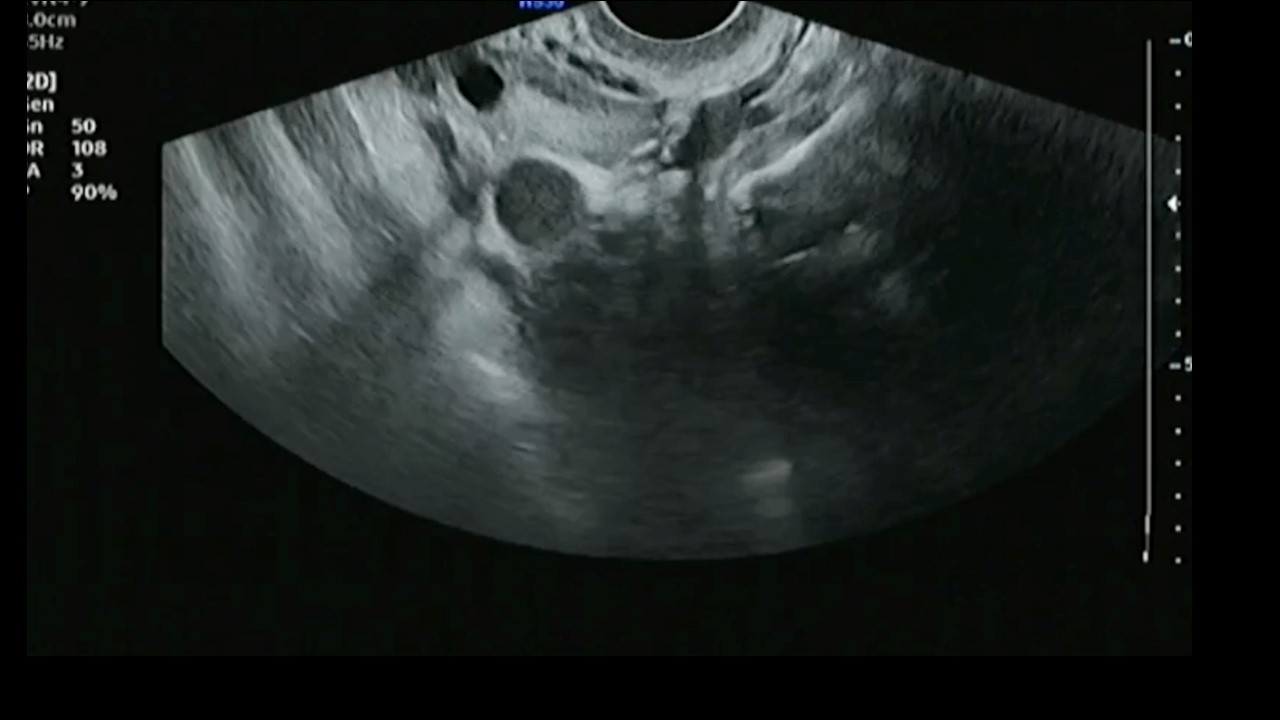

Vai trò của siêu âm trong chẩn đoán và điều trị hiếm muộn